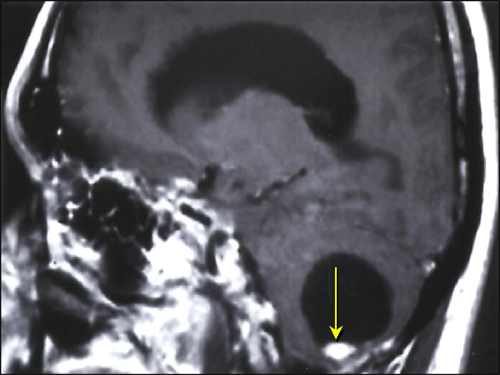

Bilateral Pheochromocytomas In Von Hippel Lindau(VHL) disease

Ni-Chin Tsai, 6th year Gillian Lieberman, MD Bilateral pheochromocytomas in Von Hippel Lindau(VHL) disease Ni-chin Tsai蔡妮瑾, Kaohsiung Medical University Year 6 ,Taiwan ... Read Document

von Hippel-Lindau Disease - VHL

Diagnosis of von Hippel-Lindau disease is often based on clinical criteria. Patients with a family history, and a CNS haemangioblastoma (including retinal haemangio-blastomas), phaeochromocytoma, or clear cell renal carcinoma are diagnosed with the disease. ... Read Here